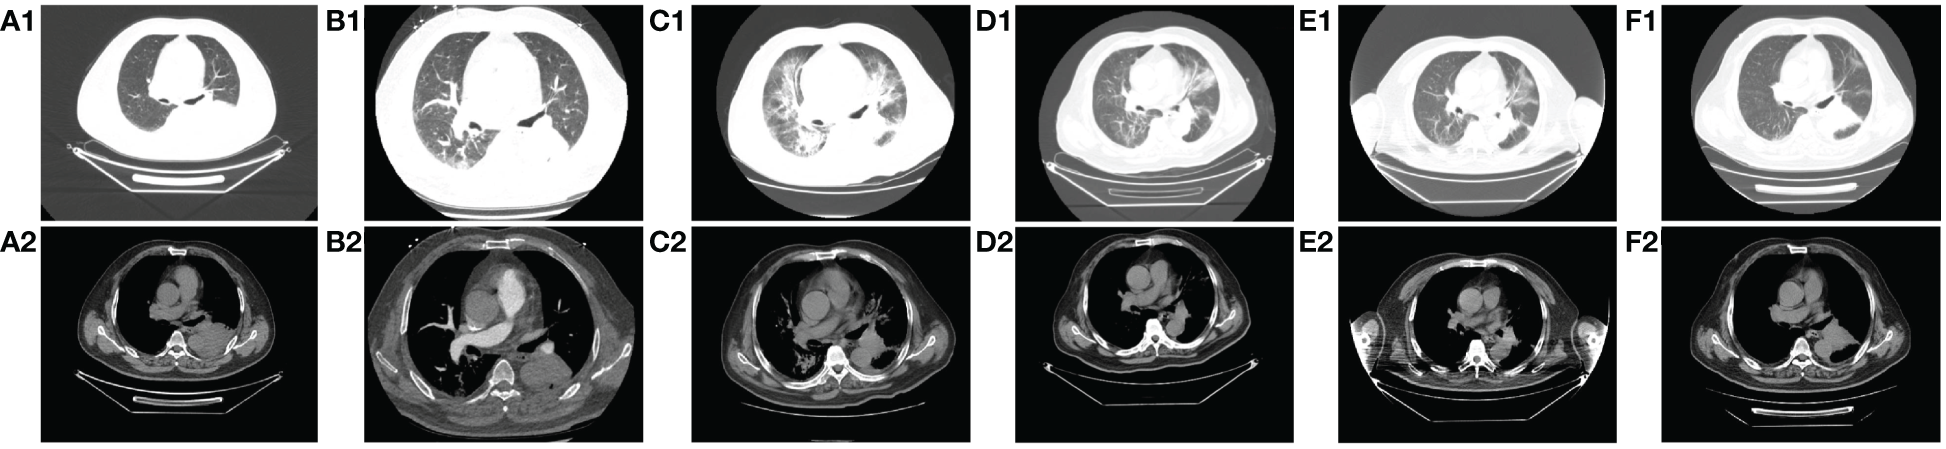

Figure 3 Comparison of CT images of patients before and after treatment with methylprednisolone and antibiotics. A1-A2: before immunotherapy (d-27); B1-B2: after 2 cycles of chemotherapy combined with immunotherapy (d45); C1-C2: immune pneumonitis before treatment with methylprednisolone and antibiotics (d88); D1-D2: day 4 after treatment of immune pneumonitis with methylprednisolone and antibiotics (d91); E1-E2: day 10 after treatment of immune pneumonia with methylprednisolone and antibiotics (d97); F1-F2: day 17 after treatment of immune pneumonia with methylprednisolone and antibiotics (d104).

On day 85, despite the continued administration of the oral dose of glucocorticoid (GCs) at 16 mg once daily, the patient once again exhibited signs of respiratory distress, including chest tightness, breathlessness, cough, and sputum production, accompanied by a fever (maximum axillary temperature of 38.7°C), and an ECOG PS score of 3. The blood neutrophil count was 7.85 × 109 cells/L (normal range, 3.5–9.5 × 109 cells/L), with an 86.80% percentage (normal range, 40%-75%). The procalcitonin (PCT) level was 0.320 ng/mL (normal range, ≤0.1 ng/mL), the IL-6 level was 171.55 pg/mL, the G test (fungal D-glucan) level was 153.55 pg/mL (normal range, ≤70 pg/mL), and the GM test was negative. Arterial blood gas analysis revealed a pH of 7.44 (normal range, 7.35–7.45), an oxygen partial pressure of 69 mmHg (normal range, 83–108 mmHg), a carbon dioxide partial pressure of 38 mmHg (normal range, 35–48 mmHg), an oxygen saturation of 94% (normal range, 95%-98%), and a bicarbonate of 25.8 mmol/L (normal range,18–23 mmol/L). Despite the administration of anti-infective, sputum, and asthma treatments, the symptoms did not improve. A chest CT scan revealed that the tumor in the lower lobe of the left lung was slightly smaller than before (Figures 3B1-B2 vs Figures 3C1-C2). Additionally, there was bilateral lung inflammation, bronchitis, emphysema, and a small amount of pleural effusion on the left side (Figures 3C1-C2). In accordance with the NCCN Guidelines for the Management of Immunotherapy-Related Toxicities, Version 1.2023, the patient was diagnosed with immune-related pneumonia (grade 3–4) combined with pulmonary bacterial and fungal infections. Methylprednisolone sodium succinate (4mg/kg/d, commenced on day 88), micafungin sodium (100 mg q.d., from day 88 to day 92), and imipenem cilastatin sodium (1 g q.8h., from day 87 to day 98) were administered. On the following day, the patient reported a significant improvement in chest tightness, cough, and other symptoms. A CT scan revealed that the inflammation in both lungs had partially resolved after four days (Figures 3D1-D2) and nearly completely by the 17th day (Figures 3F1-F2 and Figure 4). Thereafter, the GCs dosage was gradually reduced over a 6-week period, and the aforementioned conditions did not recur. All treatments were administered in accordance with the patient’s informed consent.

Following two cycles of chemotherapy in combination with ICIs, the patient developed myasthenia gravis (irAEs grade 3), myocarditis (irAEs grade 4), and hepatitis (irAEs grade 3). However, the indicators of myocardial injury and liver enzyme levels returned to normal after GCs treatment (Figures 4A, B). Unfortunately, during the GCs taper, the patient developed pneumonia (irAEs grade 3–4, as shown in Figures 3C1-C2). The condition experienced a substantial improvement following the administration of high-dose GCs, immunoglobulin, and antibiotics (Figures 3D1-F2).